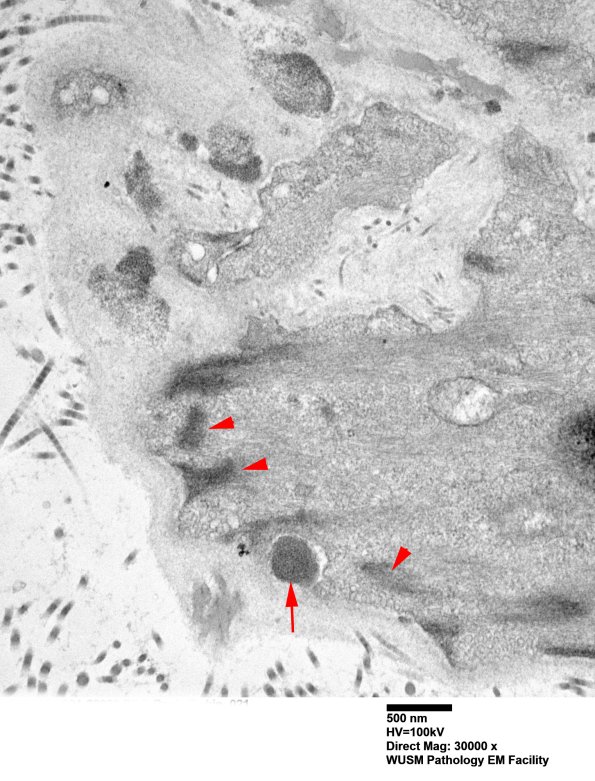

11C3B Higher magnification of image #11C3A showing smooth muscle dense bodies (arrowheads) and granular osmiophilic material (arrow). (electron micrograph)